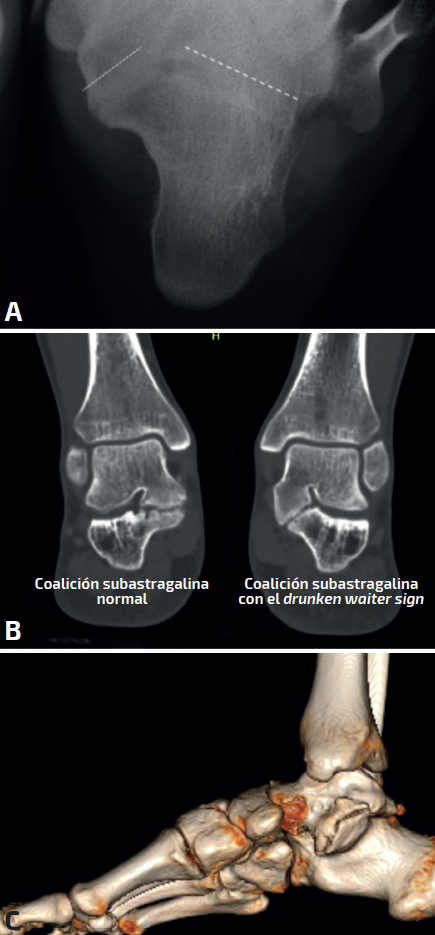

Ocasionalmente, la radiografía axial del calcáneo o proyección de Harris nos permitirá ver con mayor detalle las coaliciones TC, pero se realiza cada vez menos en detrimento de la tomografía axial computarizada (TAC) o la resonancia magnética (RM).

Drunken waiter sign o signo del “camarero borracho” (Figura 5): si se aprecia en las radiografías axiales del calcáneo de Harris un ángulo superior a 20° entre la superficie del sustentaculum y la posterior, se sospechará una coalición, con una sensibilidad del 72% y una especificidad del 94% que se debe confirmar en cortes coronales de TAC.